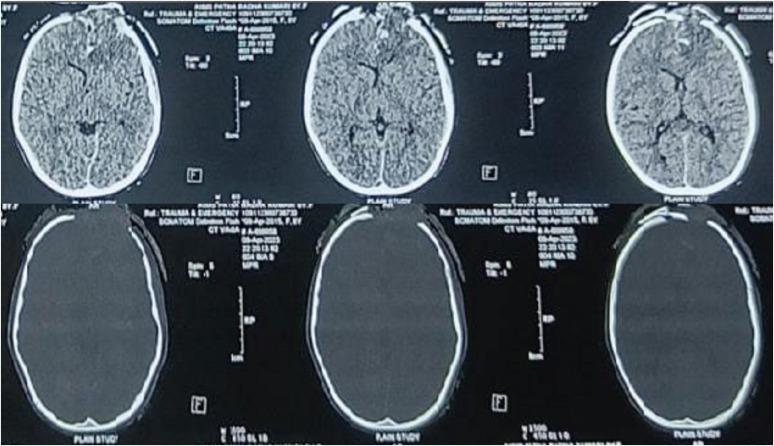

Farm-related head injuries are a significant cause of death and disability in rural households. Traumatic brain injury can result in long-term disability. The use of modern farming equipment has increased in the Indian agricultural sector over the last few decades. Machines such as threshers and winnowing devices can cause open skull fractures or scalp avulsions, while the fall of heavy tools may lead to severe head trauma. Farm animals such as bullocks and horses can also inflict traumatic brain injuries with their pointed horns, through trampling, kicking, or rarely biting. We present a case series of four patients who sustained head injuries due to farm-related accidents. All patients sustained compound cranial fractures with underlying brain parenchymal injuries, and three of them achieved complete recovery following timely medical intervention.

与农场相关的头部损伤是农村家庭死亡和残疾的一个重要原因。创伤性脑损伤可导致长期残疾。在过去几十年里,印度农业部门现代农用设备的使用有所增加。脱粒机和扬谷设备等机器可导致开放性颅骨骨折或头皮撕脱伤,而重型工具掉落可能导致严重的头部创伤。公牛和马等农场动物也可能用它们的尖角、通过踩踏、踢踹或极少情况下的撕咬造成创伤性脑损伤。我们报告了一系列4例因与农场相关的事故而头部受伤的患者。所有患者均发生复合性颅骨骨折并伴有潜在的脑实质损伤,其中3例经及时医疗干预后完全康复。